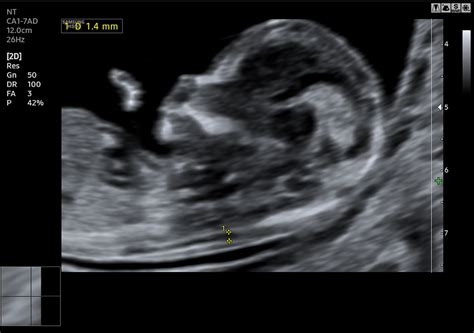

A magzati szív-ultrahangvizsgálat (vagy más néven magzati echocardiográfia) egy speciális ultrahangvizsgálat, amelynek célja a magzati szív anatómiájának és működésének részletes értékelése.

A vizsgálat során részletes képet kapunk a magzati szív anatómiájáról, beleértve a kamrákat, a pitvarokat, a szívbillentyűket és az erek rendszerét.

A vizsgálat lehetővé teszi a magzati szív működésének követését, például a szívritmus, a szívverések számának és erősségének értékelését.

A magzati szív-ultrahangvizsgálat segítségével azonosíthatók a szívrendszeri rendellenességek vagy szívfejlődési rendellenességek, például szívbillentyű problémák, septum-rendellenességek (szívfal rendellenességek), vagy egyéb szívhibák.

A vizsgálat során a szakember megvizsgálja a magzati szív szállító artériáit, például a bal és a jobb aortát.

A szív anatómiai vizsgálatának optimális időpontja a várandósság 19-22. hete.

A magzati szívultrahang, más néven magzati echokardiográfia egy kifejezetten a szívfejlődési rendellenességek kiszűrésére alkalmas vizsgálat, mellyel csaknem az összes súlyos szívfejlődési rendellenesség kimutatható.

A magzati szívultrahang eredményei színes képekben láthatóak.

A magzati szívultrahang-vizsgálatra klasszikusan a várandósság 19. és 21. hete között kerül sor.

Nehéz diagnosztikai vizsgálat, így csak speciális ultrahangos képzettséggel végezhető el.

A szív anatómiájának értékelése: A vizsgálat során részletes képet kapunk a magzati szív anatómiájáról, beleértve a kamrákat, a pitvarokat, a szívbillentyűket és az erek rendszerét.

Szív működésének értékelése: A vizsgálat lehetővé teszi a magzati szív működésének követését, például a szívritmus, a szívverések számának és erősségének értékelését.

Rendellenességek korai felismerése: A magzati szív-ultrahangvizsgálat segítségével azonosíthatók a szívrendszeri rendellenességek vagy szívfejlődési rendellenességek, például szívbillentyű problémák, septum-rendellenességek (szívfal rendellenességek), vagy egyéb szívhibák.

Szállító artériák értékelése: A vizsgálat során a szakember megvizsgálja a magzati szív szállító artériáit, például a bal és a jobb aortát.

Korszerű ultrahang készülék segítségével lehetőség van a szívben áramló vér irányának és sebességének mérésére is, mellyel a szűrés hatékonysága tovább emelhető.